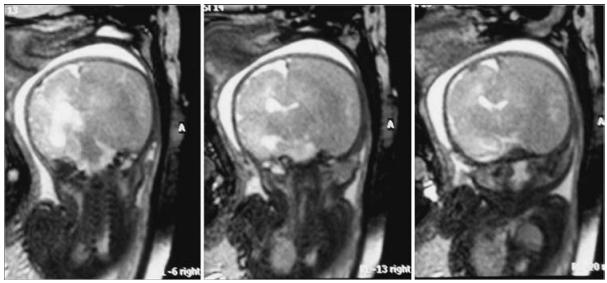

在创伤10天后前往Di Rocco教授所在的医院进行产前MR影像学评估,发现右侧脑血肿(硬脑膜下血肿)较大,压迫同侧脑室,导致中线移位;且左侧脑室稍大(12.5 mm,图1)。34周时进行检查,脑室肿大增加(9 × 17 mm)。此时距离预产期仅剩几周,但由于颅内外出血,情况十分危险,Di Rocco教授表示她必须接受剖腹产手术。

图1:孕31周胎儿MR图像显示,右侧大脑半球有一个巨大的颅内脑血肿移位。右侧脑室向对侧移位,左侧脑室轻度增大。